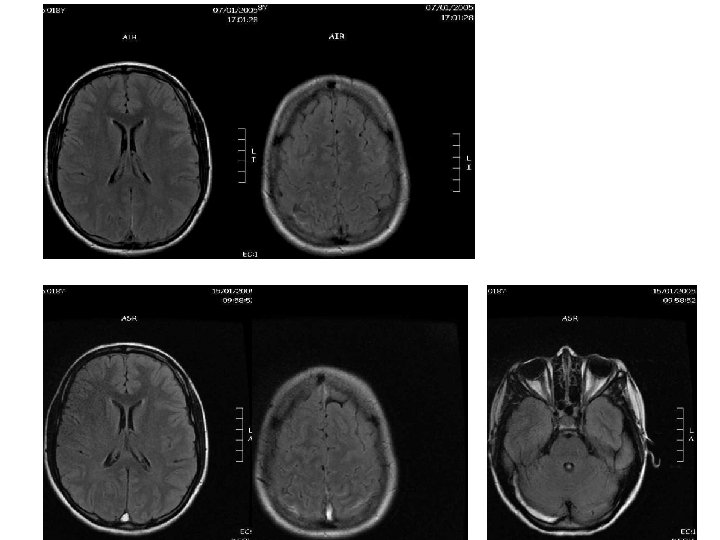

• B. Julie, 18 ans • 7/01/05 – Céphalées – Sd pyramidal – 38° – OP 45

diagnostic J 7 46

47

3 mois 48